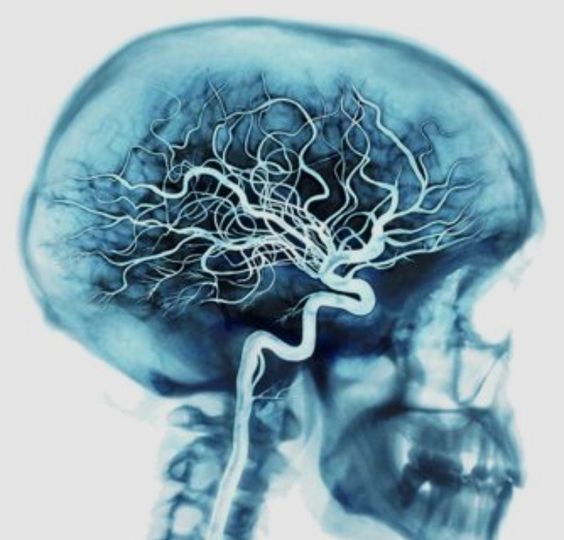

Магнитно-резонансная ангиография головного мозга - что это?![Ангиография]()

МРТ головного мозга в режиме ангиографии позволяет изучить патологию интра- и экстракраниального сосудистого русла (чаще применяется при наличии противопоказаний к МСКТ), исследовать патологическое кровоснабжение тканей мозга, которое всегда встречается при развитии опухолей.

МР-ангиография сосудов головного мозга и шеи проводится главным образом:

- при наличии или подозрении на злокачественный/доброкачественный процесс в мозге;

- для выявления свежих очагов рассеянного склероза;

- для оценки дегенеративных процессов мозга, сосудистых мальформаций и аномалий развития мозга (врожденных и приобретенных);

- при кровоизлиянии в мозг при прошествии минимум трех суток;

- стенозы, тромбозы, аневризмы сосудов шеи.

Основная причина многообразия показаний для МР-ангиографии сосудов головы - это невозможность проведения биопсии обнаруженного очага в мозге до хирургического вмешательства. В таких ситуациях Gd-содержащий препарат позволяет улучшить визуализацию в 75 % случаев, уточнить диагноз- в 71% случаев, изменить его- в 28%, что чрезвычайно важно для выбора лечения и прогнозирования исхода.